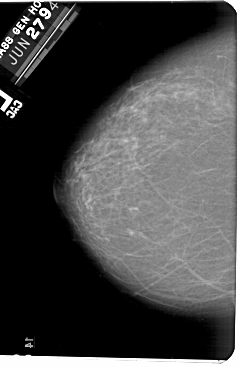

A_1561_1.RIGHT_CC

RIGHT_MLO LINES 5491 PIXELS_PER_LINE 3481 BITS_PER_PIXEL 12 RESOLUTION 43.5 OVERLAY